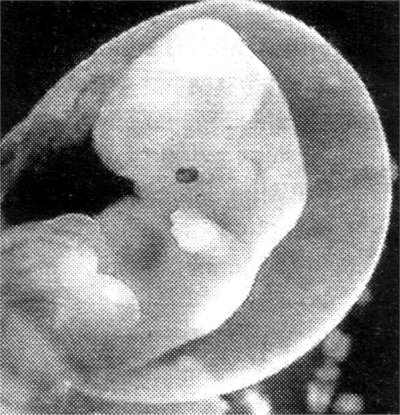

Embrião

com cinco a seis dias |

5. Se o objectivo é

fazer clonagem terapêutica, o embriã6 é destruído, ao serem

colhidas as células estaminais que se podem transformar em todos

os órgãos e tecidos. De futuro, espera-se poder criar em laboratório

órgãos para transplantes.

6. Se o objectivo fosse

fazer nascer um bebé, o embrião seria implantado num útero,

para se desenvolver. A taxa de sucesso da clonagem de mamíferos

adultos, no entanto, é de apenas 1 por cento.

7. Com a tecnologia

actual, a maioria dos embriões ou fetos morrem durante a gestação,

com malformações, ou pouco depois do parto.

Mesmo os clones que

sobrevivem ao nascimento parecem ser mais velhos do que a sua

idade, porque foram criados a partir de células de indivíduos

adultos — como acontece com a ovelha Dolly, que além de obesa

tem artrite.